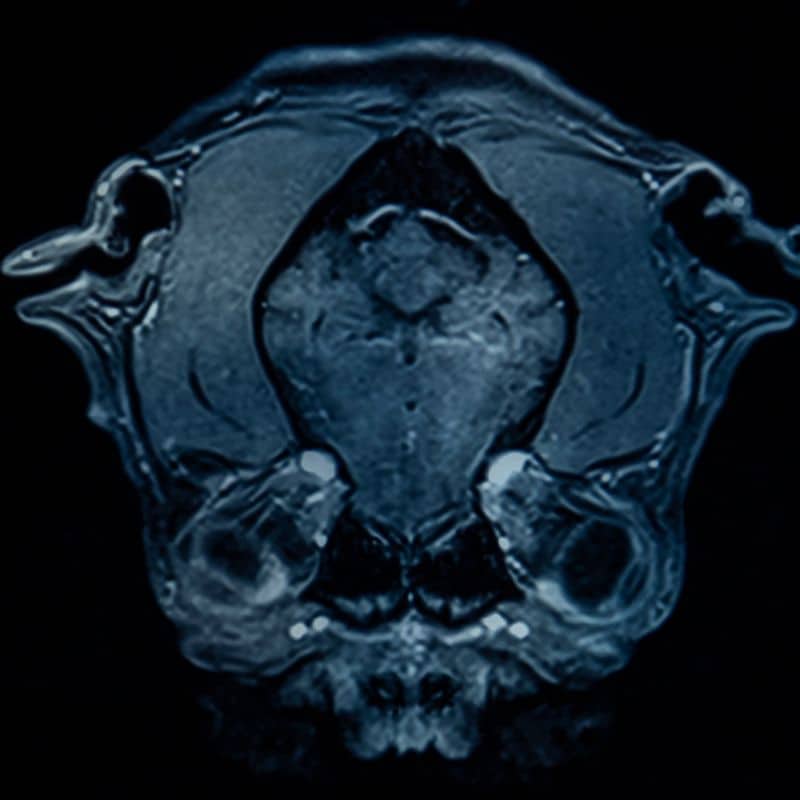

La resonancia magnética (RM) es una técnica de imagen médica avanzada que utiliza campos magnéticos y ondas de radio para obtener imágenes detalladas del interior del cuerpo. A diferencia de otras pruebas, no utiliza radiación, lo que la hace segura para la mayoría de los pacientes. Permite observar tejidos blandos, órganos, articulaciones, cerebro, médula y vasos sanguíneos con gran precisión.

La resonancia magnética sirve para diagnosticar y controlar numerosas enfermedades y lesiones, como problemas articulares, neurológicos, cardiovasculares o tumorales. También se utiliza para planificar tratamientos y evaluar su eficacia, ayudando a los médicos a tomar decisiones más precisas y personalizadas para cada paciente.

La resonancia magnética (RM) es una técnica de diagnóstico por imagen avanzada que utiliza campos magnéticos y ondas de radio para obtener imágenes detalladas del interior del cuerpo. A diferencia de otras pruebas, como los rayos X o la tomografía, la resonancia magnética no emplea radiación, lo que la convierte en un método seguro y preciso para estudiar tejidos blandos, órganos, articulaciones, cerebro, columna y vasos sanguíneos.

Se utiliza para diagnosticar, controlar y planificar el tratamiento de múltiples enfermedades, incluyendo problemas musculoesqueléticos, neurológicos, cardiovasculares o tumorales. Gracias a su capacidad para generar imágenes de alta resolución, permite a los médicos detectar lesiones y anomalías que otras técnicas podrían pasar por alto, asegurando un diagnóstico más completo y fiable.